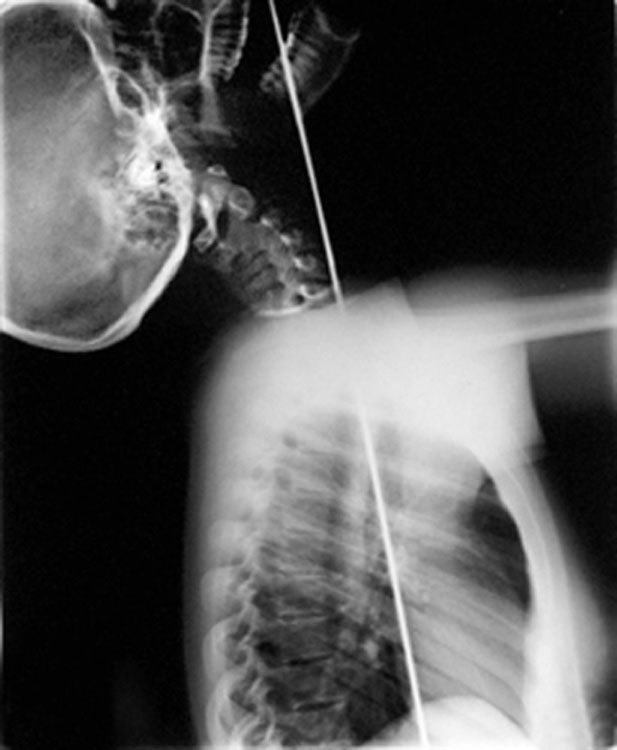

Experience the breathtaking sight of our sword swallower as she effortlessly slides a massive sword down her throat without a scratch! Our female sword swallower is among the pioneers to swallow real flowers, adding an incredible twist to her already astonishing act. Combining the art of sword swallowing with magic in a unique and stylish manner, she offers a gripping performance that captivates all who watch.